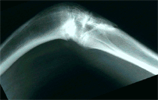

Progress

Knee flexion corrected with tibia frame applied